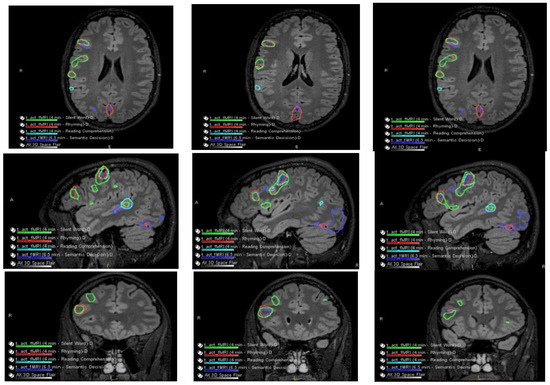

The patient had a functional MRI scan of the brain. This showed no change in the probable cortical dysplasia of the posterosuperior right temporal lobe at its junction with the angular gyrus. There was strong right cerebral hemispheric language lateralization. The right Wernicke area was just inferior to the presumed cortical dysplasia, although it was noted that language function could extend into the dysplastic cortical region with at least some language tasks (Figure 2 and Figure 3).

Figure 2.

Language and Verbal Memory fMRI Testing. There were no obvious perfusion abnormalities. During cerebrovascular reactivity (breath hold), there was no cerebrovascular reactivity abnormality evident.

Co-localization of language-related activity with the silent word, rhyming, and reading comprehension tasks is also centered at the posterosuperior portion of the right pars triangularis. This is visualized on axial slides (ROW 1), sagittal slices (ROW 2), and coronal slices (ROW 3) suggestive of a right-sided Broca area. Other more posterosuperior right language-related activations are also seen with all 4 language tasks.

Language-related activation strongly lateralized to the right cerebral hemisphere with all four language tasks. The co-localization of activation centered at the posterior aspect of the right superior temporal sulcus with all four language tasks, which is suggestive of a right-sided Wernicke area (e.g., see overlaid summary maps axial sagittal coronal, respectively, in ROW 1).

With three of the four language tasks, areas of right Wernicke activation are very near each other in the right temporo-parietal-occipital cortex. These are within a centimeter, essentially abutting the inferior aspect of the adjacent presumed cortical dysplasia, although with the fourth (reading comprehension) task, language activation extends to/into the posterolateral aspect of the presumed cortical dysplasia (ROW 2). Of course, the volumes of these language-related activations as visualized on these maps are rather arbitrarily set by adjusting thresholds for sensitivity and specificity.

No appreciable left cerebral language-related activation was seen with three of the four tasks. With the fourth task, i.e., the silent word generation task, there was a small amount of homologous left-sided Broca area activation and a small amount of left dorsolateral prefrontal cortex activation.